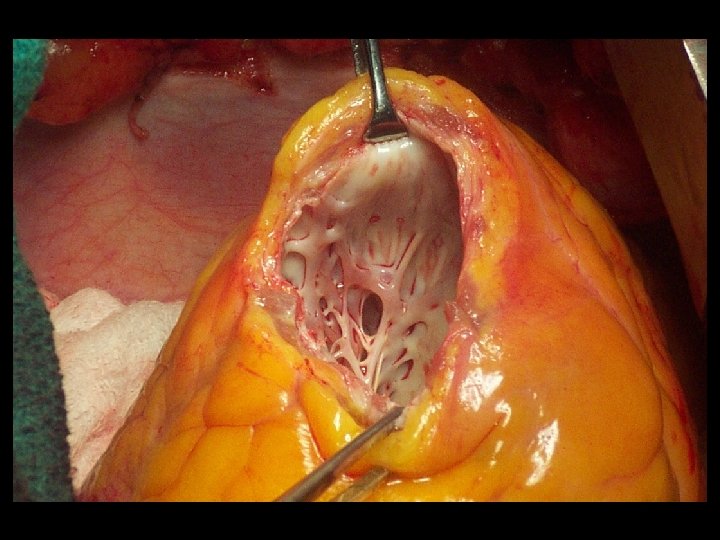

Técnica quirúrgica: cierre lineal o o Incisión en la porción mas delgada del aneurisma, paralela al surco interventricular. Excisión del área cicatricial. Suturas de tracción en cada extremo de la línea de sutura. Cierre del defecto con puntos en U separados de polipropileno No. 1 sobre líneas de felpa y refuerzo de sutura continua No. 0.

Técnica quirúrgica: plastia con parche o o Incisión en la porción mas delgada del aneurisma, paralela al surco interventricular. Jareta con sutura de polipropileno 2 -0 en la línea que demarca la cicatriz con el miocardio. Medida del defecto. Parche de dacron o pericardio (autólogo o bovino).

Técnica quirúrgica: plastia con parche o o Sutura continua del parche con polipropileno 3 -0. El remanente de la pared aneurismática es suturada linealmente sobre el parche con puntos continuos de polipropileno 2 -0.